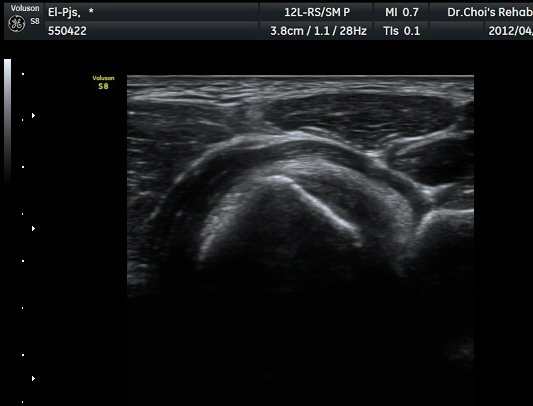

ŽÃËÀÚ¸¦ ÆÈ²ÞÄ¡ ¸»´ÜÀ¸·Î À̵¿ÇÏ´Ï À̵ιڱ٠ÈûÁÙÀÇ ºñÈÄ¿Í ÈûÁÙ ÁÖÀ§¿¡ Àú¿¡ÄÚ ¼ö¾×Àú·ù°¡ ]

°üÂûµÈ´Ù(±×¸² 2, 3, 4, 5). ŽÃËÀÚ¸¦ ¸»´ÜÀ¸·Î À̵¿ÇÒ ¶§ ŽÃËÀÚ¸¦ ¸Ó¸®ÂÊÀ¸·Î °æ»ç(tilting)½ÃÄѾß

À̵ιڱ٠ÈûÁÙ¿¡ Á÷°¢ ÀÇ ÃÊÀ½ÆÄ Á¶»ç°¡ °¡´ÉÇÏ¿© À̵ιڱ٠ÈûÁÙÀÌ °í¿¡ÄÚ·Î °üÂûµÈ´Ù.

À̵ιڱ٠ÈûÁÙ Á¾´Ü¸é°Ë»ç¿¡¼­ ÈûÁÙÀÇ ºñÈİ¡ °üÂûµÇ³ª ÈûÁÙÀÇ ¿ä°ñµ¹±â(radial tuberosity)

ºÎÂøºÎ´Â ºñµî¹æ¼ºÀΰøÀ½¿µ(anisotopic artifact) ¶§¹®¿¡ ¶Ñ·ÈÈ÷ °üÂûµÇÁö ¾Ê´Â´Ù(±×¸² 6).